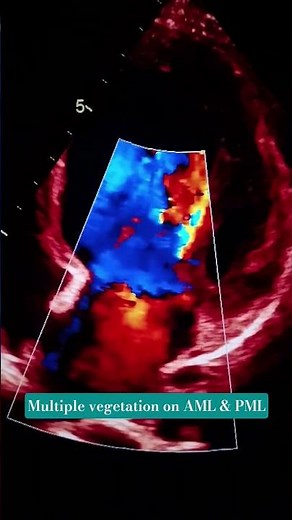

MULTIPLE VEGETATION SEEN ON AML & PML. #echocardiography #heartdisease

YouTube

Cardioman🩺

1.1K views

3 months ago

MULTIPLE VEGETATION SEEN ON AML & PML. #echocardiography #

…